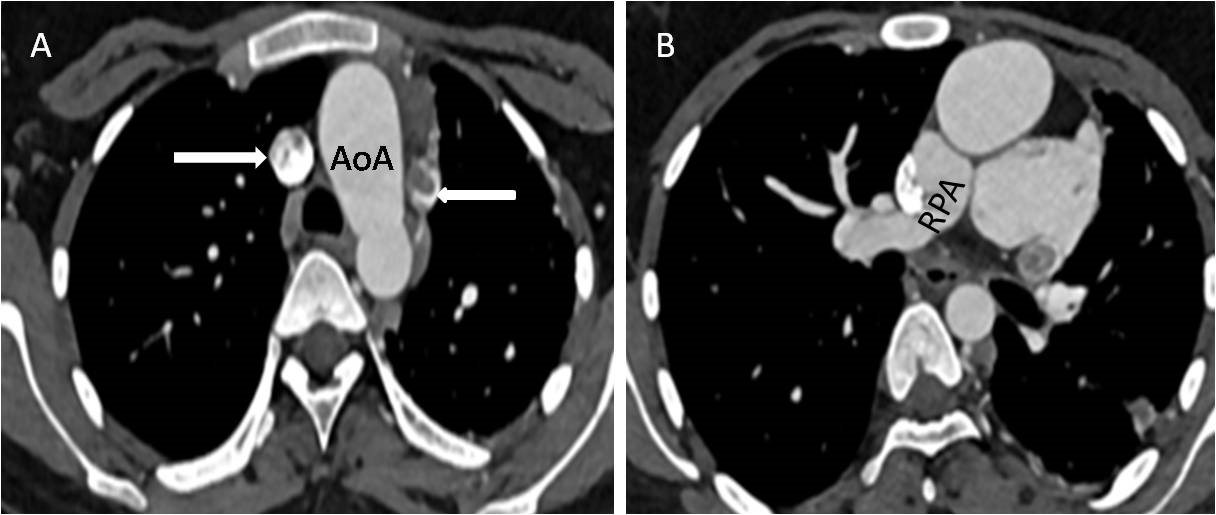

Figure 3 (A) CT angiography axial image showing left sided aortic arch (AoA), double superior vena cava (SVC) (marked by white arrow). (B) Axial CTA image depicting right pulmonary artery (RPA) with non-visualized left pulmonary artery.